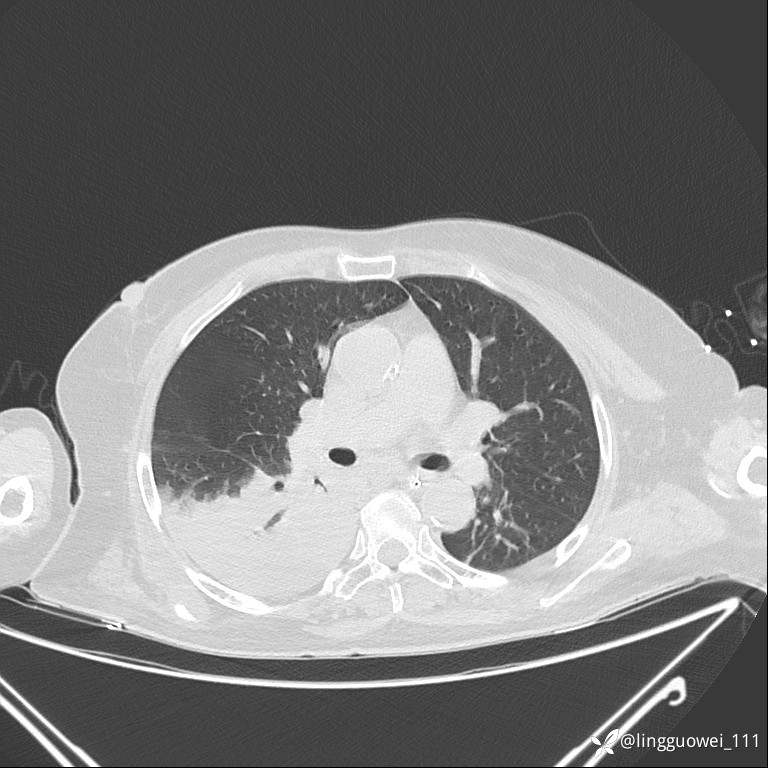

CT平扫: